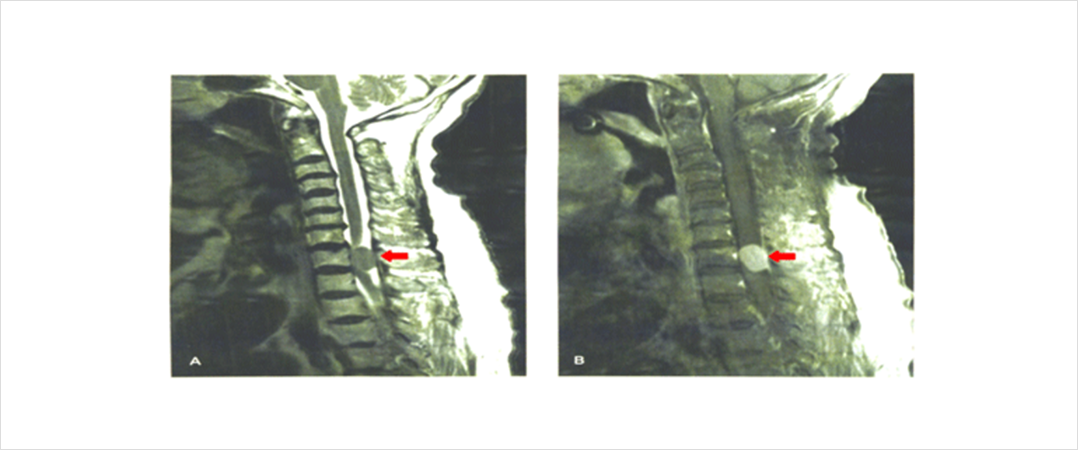

등척추 부위에 발생한 수막종의 자기공명영상 사진입니다. 화살표가 가리키고 있는 둥근 형태의 병변이 수막종으로 조영제를 사용한 우측 사진에서 종양이 밝은 회색으로 관찰되고 있습니다.